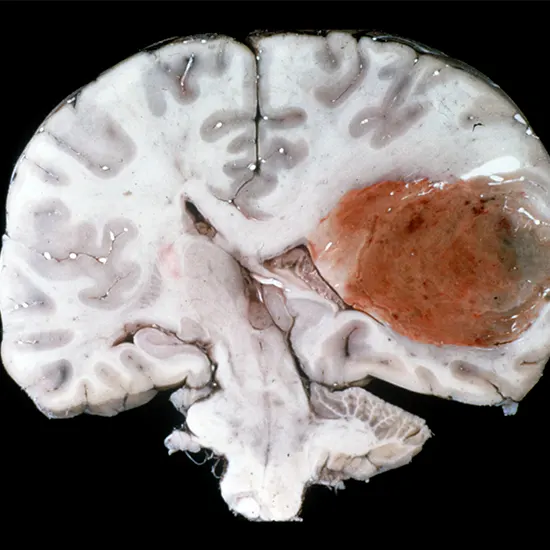

Glioblastoma, also known as glioblastoma multiforme(GBM), is a maligant and aggressive type of brain tumor that originates from glial cells, particularly astrocytes. It is the most common and aggressive type of primary brain tumor in adults, accounting for about 15% of all brain tumors.

Diagnosis of glioblastoma is typically made through imaging studies such as magnetic resonance imaging (MRI) or computed tomography (CT) scans, followed by a biopsy to confirm the tumor type.